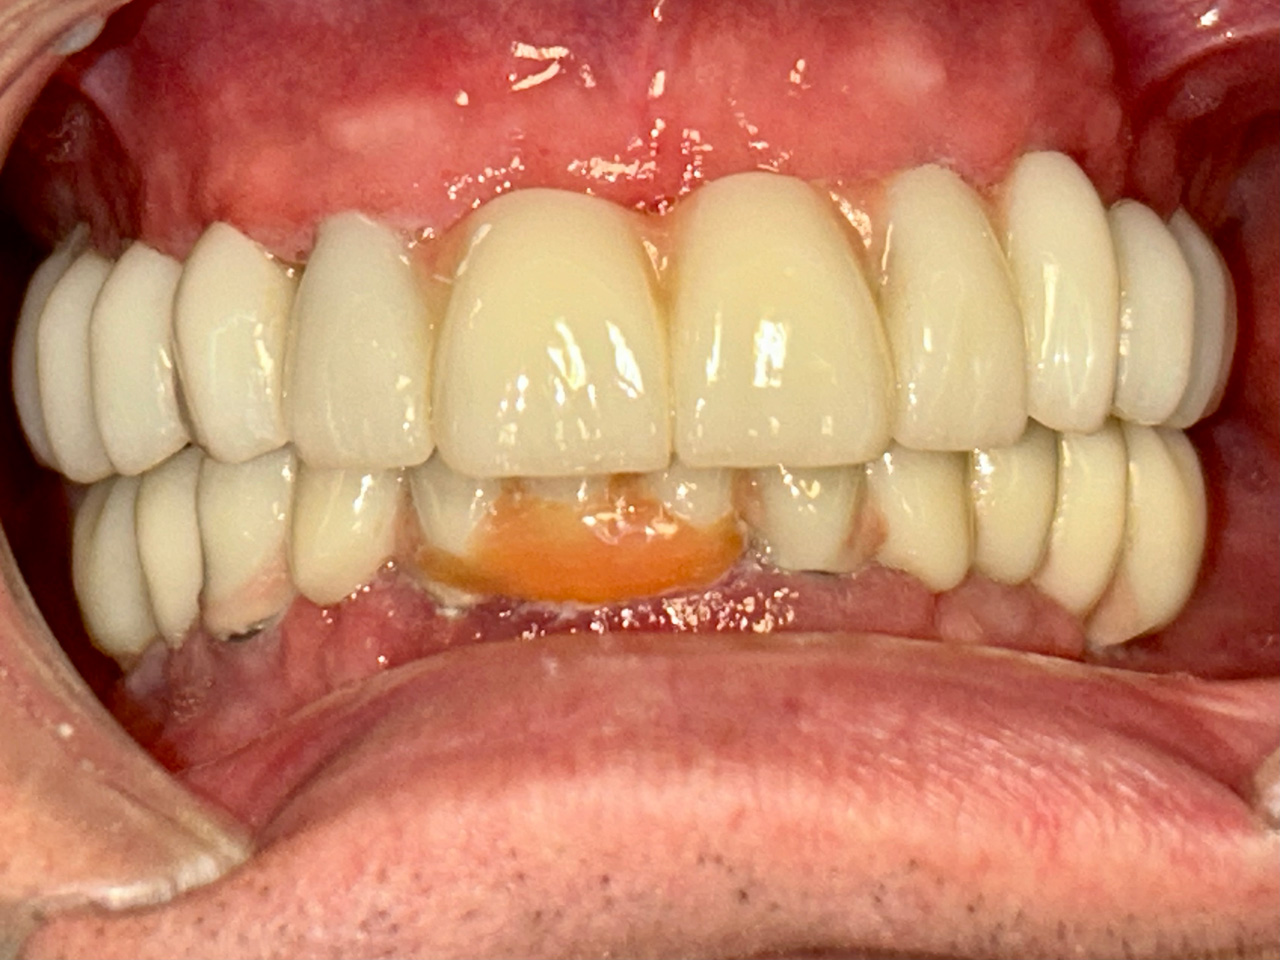

Elhanyagolt fogsor cseréje 2 nap alatt

2 nap alatt varázsoltuk ezt a szép esztétikus alsó, felső körhídat implantátumokkal megtámasztva a korábban elhanyagolt szájba. Az 1. nap 26 fogat távolítottunk el, mert annyira rossz állapotban voltak, és rögtön azonnal terhelhető IHDE svájci implantátumokat raktunk be, fentre 8, lentre 6 darabot. A sebeket összevarrtuk és intraorális szkennerrel digitális lenyomatot vettünk. 2 nap múlva pedig beragasztottuk a kész PMMA műanyag körhidakat. Dr. Kelemen Péter és a Symbion Fogtechnika munkája.